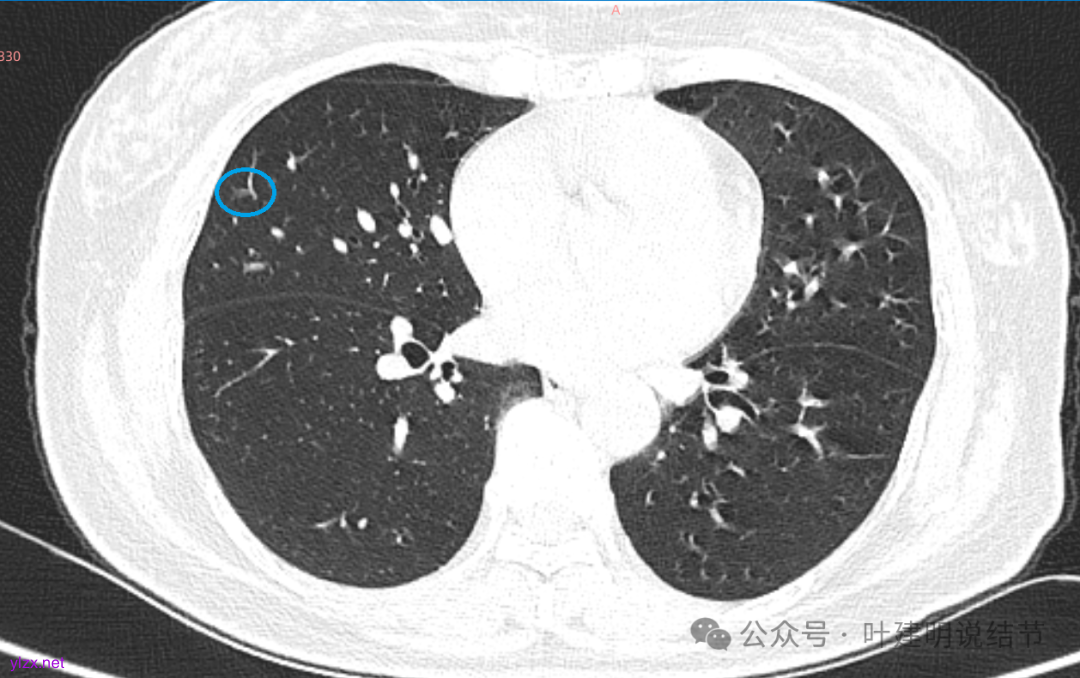

先来看2025年3月的影像:

两肺多发磨玻璃结节,我们主要看最主要的病灶有没有风险或者有没有进展就可以。我是先看2025年的,黄色的微小磨玻璃结节,密度很低,但是轮廓较为清楚,需要考虑肺泡上皮增生或者肺泡间隔增宽,严格意义上应该没有算肺癌,但是以后有可能会发展到不典型增生或者原位癌,当然也可能永远发展不到那个程度,所以目前不需要管;蓝色的到底是肺泡上皮增生还是少许慢性炎不太好确定,因为轮廓稍显模糊,但它又是磨玻璃密度,总归近期是能够随访的;橘色的密度比黄色的略高,有可能会使肺泡上皮增生或者不典型增生,目前也仍可以随访;粉色的是主病灶,位于左肺上叶,混合密度,表面毛糙,由小血管进入,单次看需要考虑微浸润性腺癌可能性较大。然后我们再来看2020年的影像,因为除了粉色的其他的都没有风险,所以不需要一一去找出来,重点关注粉色这处当时是怎样的。我们发现这个病灶5年前就有,也有小血管进入,也有表面毛糙,也是磨玻璃密度,但是当时磨玻璃当中没有实性的成分,是纯磨玻璃伴微小血管进入。对比起来看,这个病灶在5年当中略有进展,原来应该是腺体前驱病变,现在应该是原位癌或者微浸润性腺癌。那么是不是现在就到了一定得马上手术的程度呢?这个仍然可能是不同医生意见会有出入的。假如说从再随访是不是马上会转移来讲,这么小的肿瘤,发展这么慢,而且仍然含有磨玻璃成分,病理考虑与微浸润性腺癌可能性较大,应该仍然不至于说没有随访的空间。但是如果继续随反思想压力比较大,以及即便在随访后续仍然总得要开刀来说,加上病灶位置靠胸膜并不远,简单的单孔胸腔镜楔形切除就能解决问题,将有一定风险的这个病灶切了,同样是可行的。这需要你自己权衡决定。我没有办法100%给十分确切的意见。但是如果从倾向性来讲,由于是多发病灶,加上年纪还轻,风险还不是很大,稍微清一下雨6~9个月复查,有进展病风险再增加再考虑手术。意见供你参考!